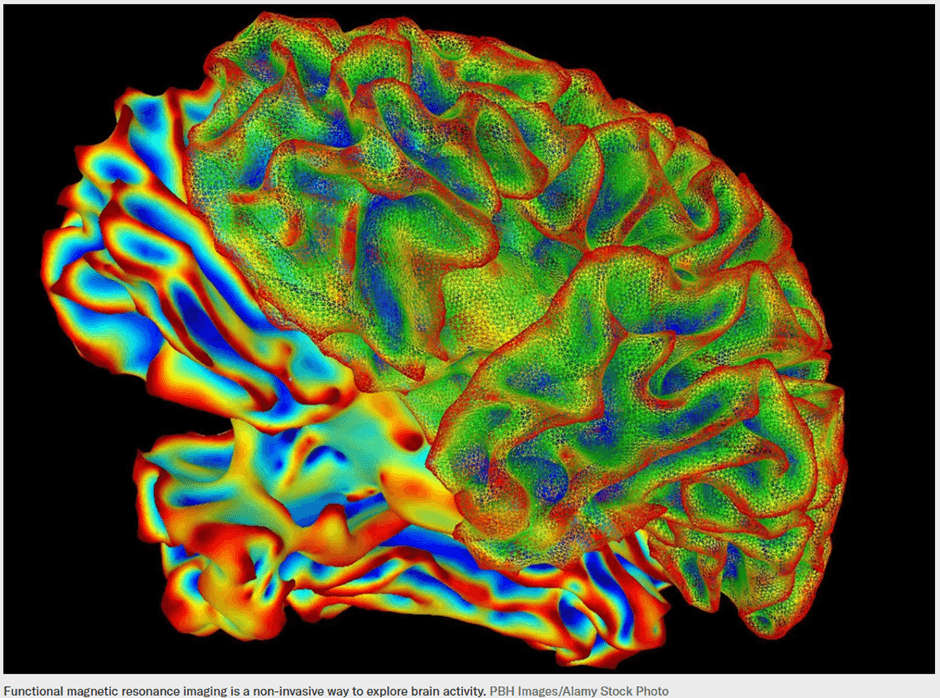

For decades, neuroscientists have attempted to peer into the brain and translate neural activity into understandable signals. While earlier research could roughly predict what a person was seeing or hearing, converting rich mental experiences into coherent language remained beyond reach. The gap between raw brain signals and meaningful sentences seemed too wide to bridge.

Recent advances in artificial intelligence, however, are beginning to close this gap. A new technique known as mind captioning suggests that the brain represents meaning in a structured form even before it is transformed into spoken or written language.

First, researchers used a deep-language model to analyze captions from more than 2,000 videos. Each caption was converted into a numerical representation, or meaning signature, capturing its semantic content rather than its exact wording. In parallel, a second AI model was trained on functional MRI data collected while participants watched these videos. This model learned to associate specific patterns of brain activity with the corresponding meaning signatures.